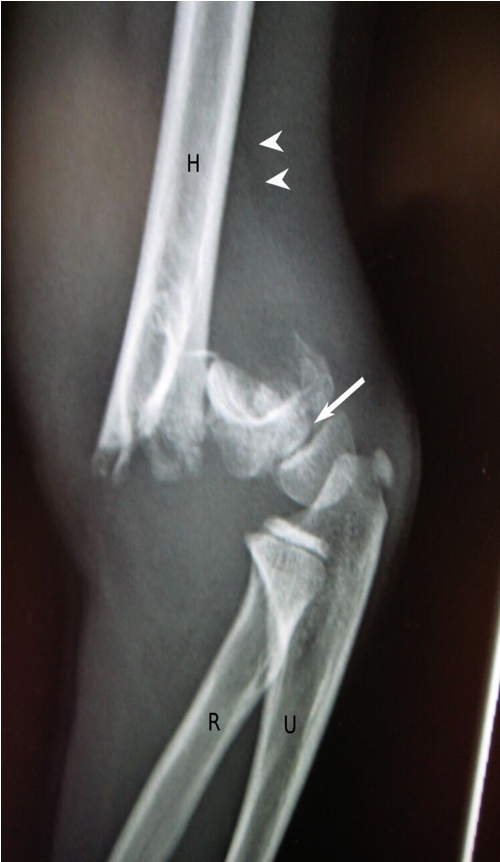

A comminuted supracondylar fracture of the distal humerus shows posterior displacement of the distal fragment and growth plate involvement (white arrow).

Joint effusion is present, with elevation of the lucent posterior fat pad (white arrowheads).

H: humerus; R: radius; U: ulna